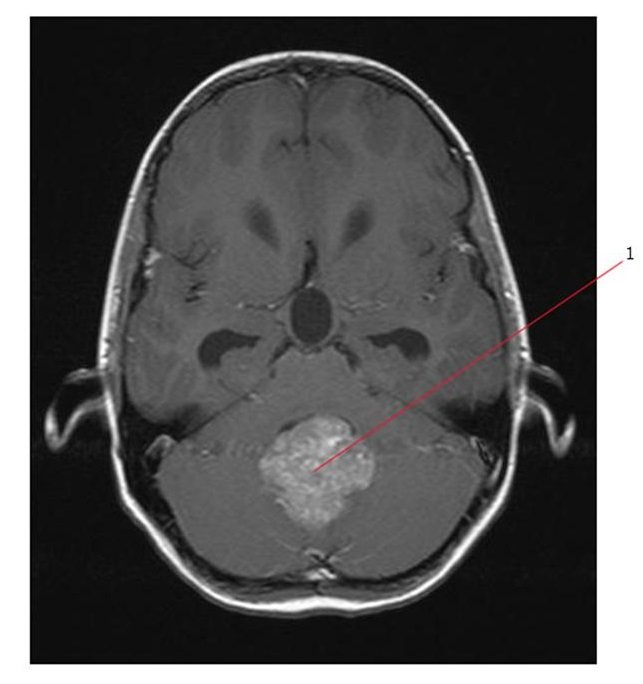

- инфратенториальные (субтенториальные) – расположенные в задней черепной ямке (Зчя), задней области головного мозга, где находятся мозжечок, ствол мозга и четвёртый желудочек.

Симптомы эпендимомы зависят во многом от её локализации. В случае инфратенториального расположения (например, опухоль находится в 4 желудочке), проявления болезни бывают особенно тяжёлыми.

- МРТ – особенно информативно при обследовании головного мозга. Снимки помогают уточнить размер, структуру и форму новообразования, выяснить состояние сосудов. МРТ безопасно для детей благодаря отсутствию излучения;